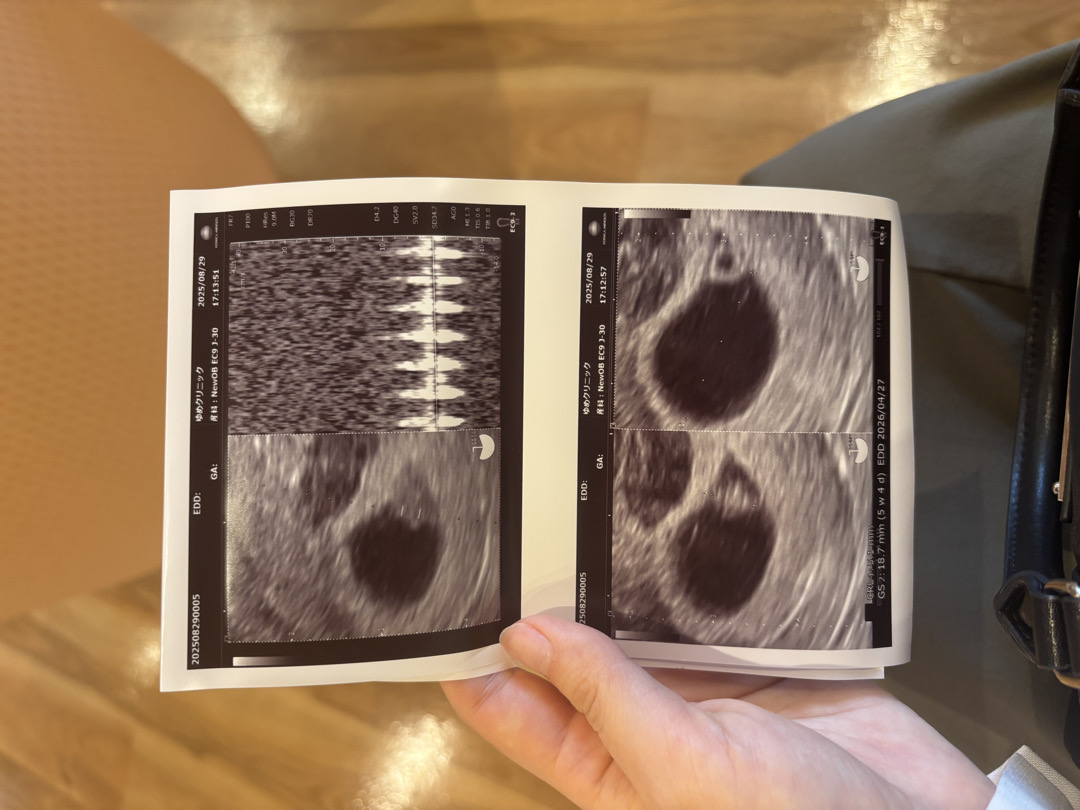

혹시 저랑 같은 이유로 고민하고 있으신 분이 있을까 싶어서 적어봐요! 전 막생이 7/5이고 주기가 36일이라 배란일이 8/2일쯤으로 늦은 편인데, 8/18일 아기집이랑 난황을 확인했어요 이틀뒤 갈색 피비침이 있어서 유산방지약(자궁수축 막아주는 약)처방 받고 아기집,난황 확인후 돌아왔는데 빨간피도 보았고 생리 끝물처럼 이틀 내내 피가 나왔습니다 걱정되서 가까운 다른 병원에 가보니까 벌써 7주차 정도 되었을 때인데 아기집이 텅텅 비었다고 이틀 전 확인한 난황도 없다고 했어요 계류유산이라는 말을 듣고 며칠 뒤에오면 유산 확진 할 수 있고 수술해야한다고 하더라고요 원래 다니던 병원 정기 검진일이 일주일 뒤에 있어서 그냥 자포자기 심정으로 일주일 보내고 있었는데 어제 검진에서 건강한 5미리 아기랑 심장소리도 듣고 왔네요!! 초음파 이상있다고 이야기 들으시면 절대 한곳에서만 보지 마시고 다른 병원가보세요 초기엔 아직 아기도 작고 초음파 각도에 따라서 안보이는건데 바로 유산 진단내리는 병원도 있으니까요… !!